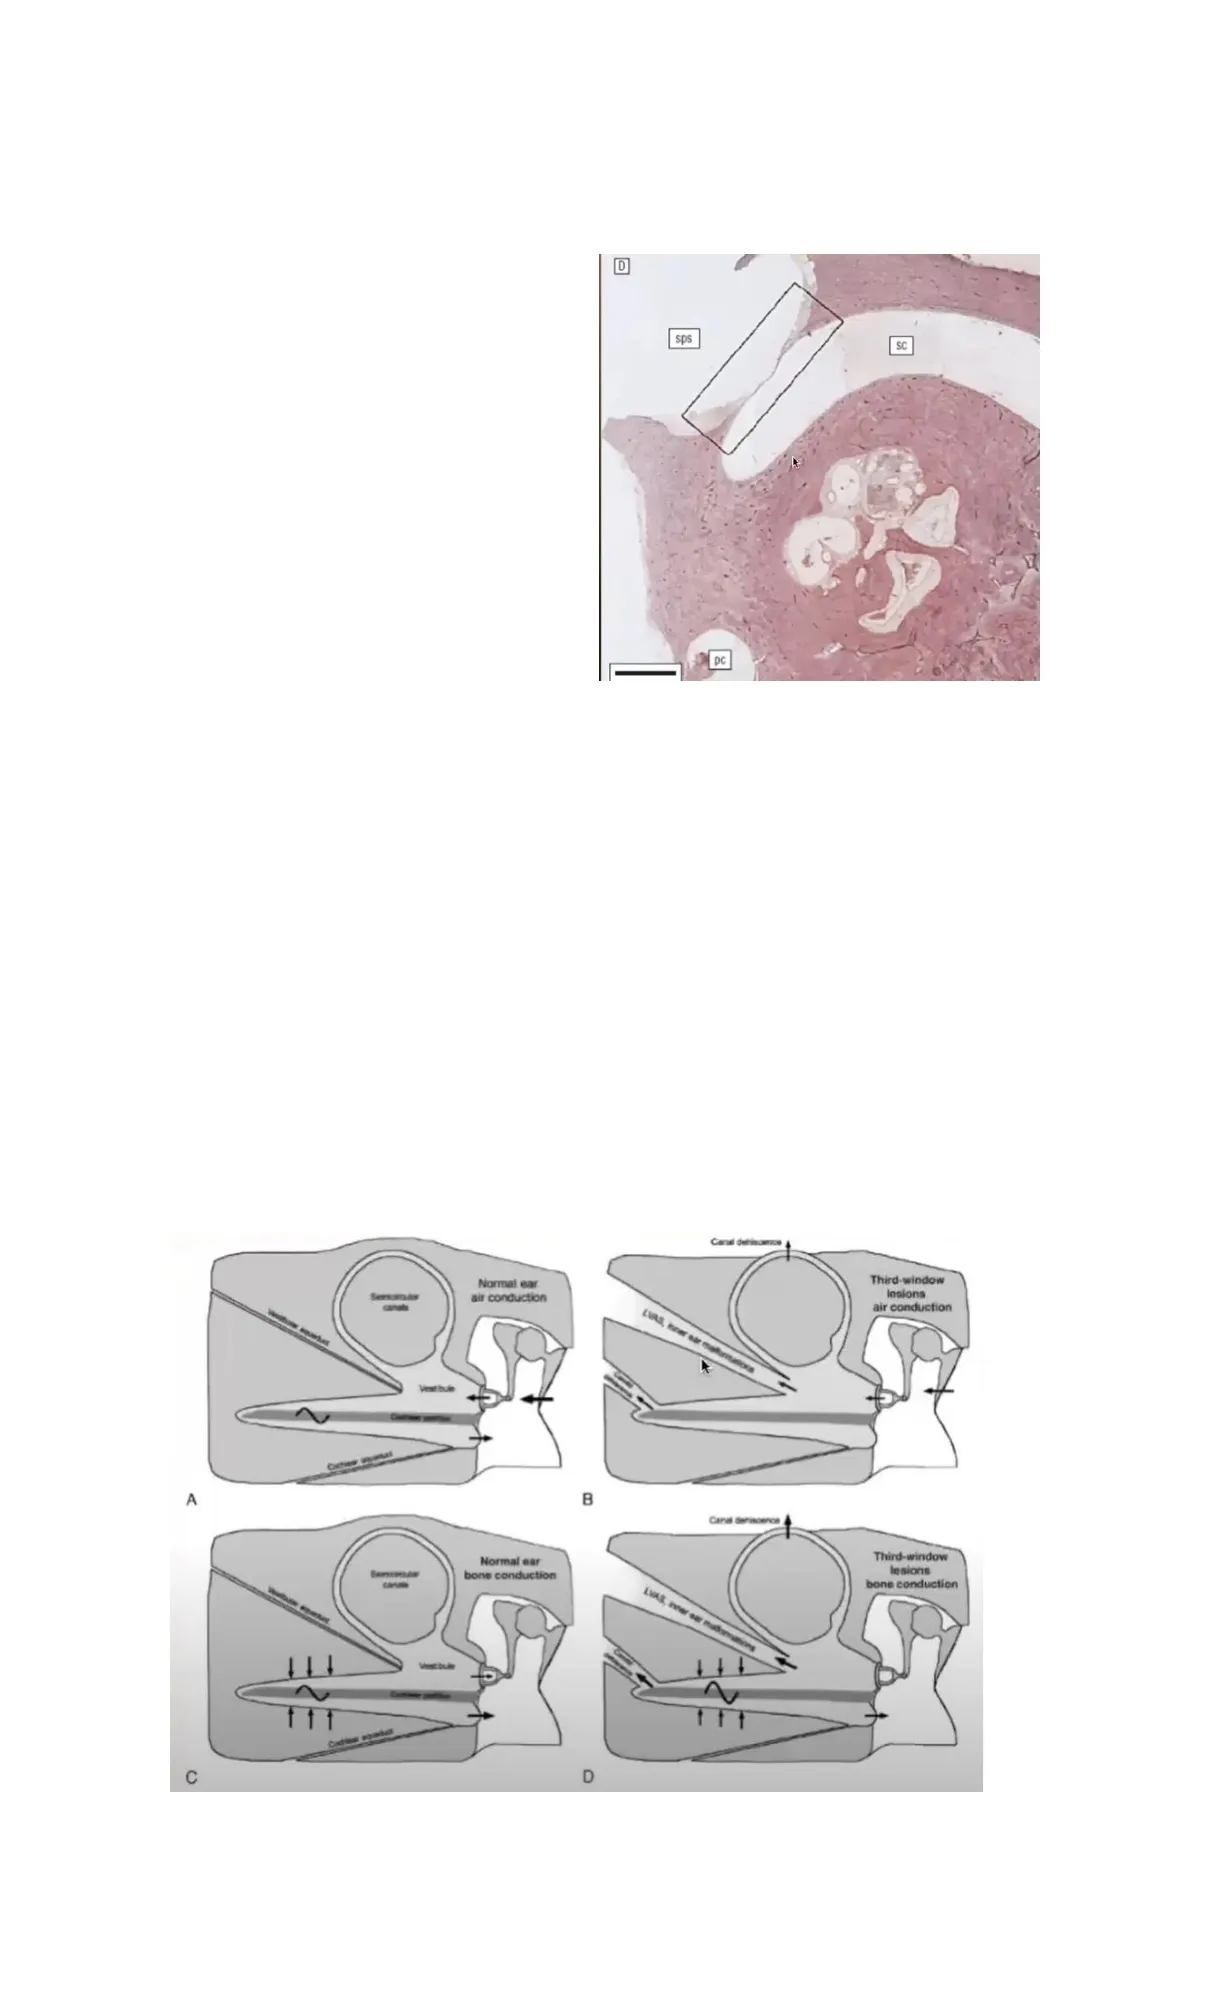

Corte histológico en donde se puede observar

la cápsula ótica (hueso compacto y firme, de

los más duros que tenemos). Podemos

observar un adelgazamiento de la cápsula

ótica dejando una fina capa de endostio y una

capa del laberinto membranoso que queda

expuesto a la presión desde afuera y desde

adentro para así generar cambios en la presión

dentro del canal.

La dehiscencia actúa como tercera ventana en el oído interno, derivando energía acústica desde la

cóclea a bajas frecuencias, permitiendo al csc responder a estímulos de sonido y presión, es decir, el

csc puede responder a estímulos de sonido por la ventana oval o por la dehiscencia (por ejemplo,

aumento de la PIC o valsalva).

Lo normal es que la onda acústica llega a la rampa vestibular y sale por la rampa timánica por la

membrana timpánica secundaria y se acaba la onda. Cuando hay patología, parte de esa onda no

llega a la membrana timpánica secundaria, sino que se va por la dehiscencia (o por acueducto

vestibular agrandado) y de esa manera, la fuerza que llega a la membrana timpánica secundaria llega

con menor intensidad y se genera este fenómeno físico en donde hay una hipoacusia de conducción

secundaria.

Canal derisorse

Normal ear

air conduction

Sersoro dos

Third-window

lesions

Vestibule

-

A

B

Canal deriscence

bone conduction

Mest bule

C

EVAS, inner ear matormations

D